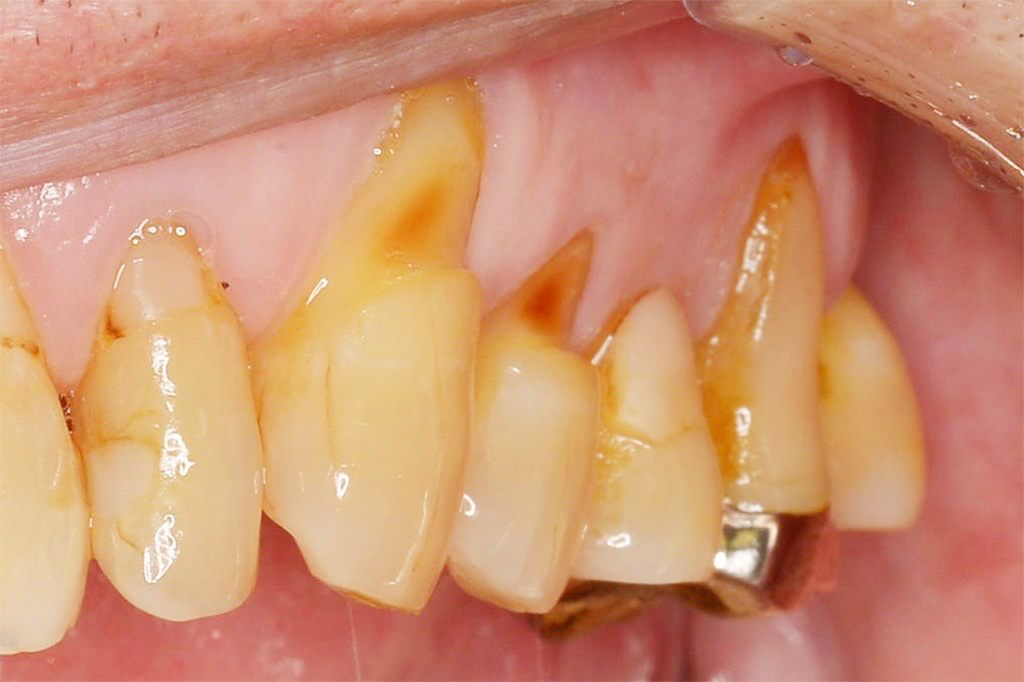

臨床でよく見る歯頸部のくさび状欠損。

以前は「アブフラクション」と

習った方も多いのではないでしょうか?

しかし現在は、

NCCL(Non-Carious Cervical Lesion)

という用語が主流になっています。

アブフラクションとは、

咬合力による歯のたわみ(応力集中)で

歯頸部が破壊されるという理論

のことです。

つまり、

「力」が主原因という考え方でした。

研究が進むにつれ、

原因は一つではないことが

分かってきました。

現在は、

=非う蝕性歯頸部病変

という包括的な名称が使われます。

これは、「むし歯ではない歯頸部の欠損」を

まとめて表す言葉です。